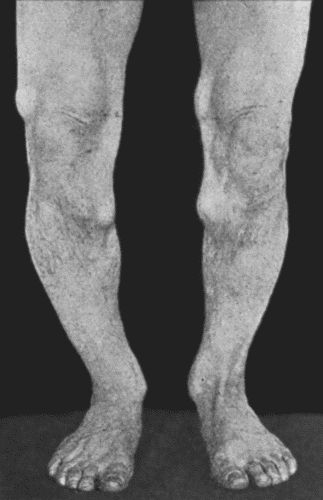

67.Extensive Varix of Internal Saphena System on Left Leg 291

68.Mixed Nævus of Nose 296